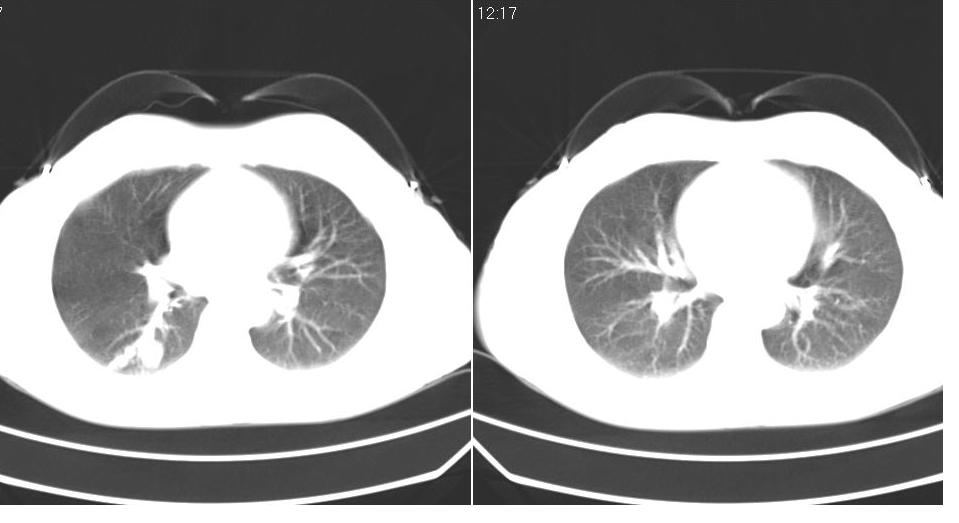

女 40岁,胸片体检发现右肺肿块,无任何症状。

考虑右肺下叶继发肺结核或炎症可能?

下叶背段多发性小腺泡结节,考虑结核。

考虑右肺下叶继发性肺结核!

考虑右肺下叶背段继发性肺结核。